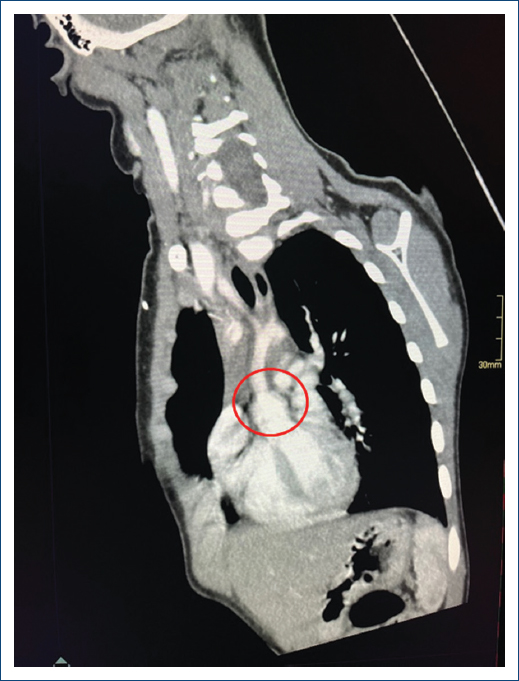

Complementary studies included a chest X-ray that revealed excavation of the lung button (Fig. 1) with no other relevant findings. The electrocardiogram showed ST depression, left ventricular growth with a positive Sokolow-Lyon index, suggesting signs of systolic overload and myocardial ischemia. The two-dimensional transthoracic echocardiogram confirmed concentric left ventricular hypertrophy; normal mobility; preserved ejection fraction of 70%; tri-leaflet aortic valve without alterations; the presence of severe SVAS with a maximum gradient of 116 mmHg and a mean gradient of 65 mmHg. The aortic annulus measured 10 mm (z-score-1.7); the sinuses of the Valsalva measured 14mm (z-score –1.3); and STJ measured 8 mm (z-score –3.6) (Fig. 2). These findings were confirmed with chest angiotomography (Fig. 3). Based on these findings, the diagnosis of SVAS was confirmed, and the decision was made to perform Doty’s procedure to resolve the stenosis. The girl is currently asymptomatic with regular cardiovascular follow-ups every 6 months.

Figure 3. Chest angiotomography, orthogonal and long-axis plane of the aortic roof, demonstrating the typical hourglass image (red circle), with an annulus of 17 mm (z 0.38) and an STJ of 8.8mm (z-3.6).